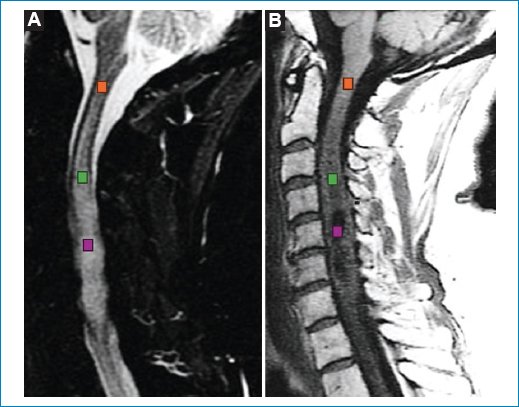

Figura 6. (A) Regiones de interés sobre una secuencia sagital ponderada para T2. (B) Regiones de interés sobre una secuencia sagital STIR. Naranja: normal. Verde: polo superior del tumor. Violeta: centro del tumor.

La varianza fue la métrica de textura que mostró la mayor desviación respecto al tejido normal en todas las secuencias analizadas, seguida por la media de intensidad y la curtosis, especialmente en T2 y STIR.

Se realizó un análisis de textura69 (Tabla 1, Fig. 6) donde la varianza fue la métrica de textura que mostró la mayor desviación respecto al tejido normal en todas las secuencias analizadas, seguida por la media de intensidad y la curtosis, especialmente en T2 y STIR. La varianza, como métrica con mayor desviación respecto al tejido normal, sugiere una marcada heterogeneidad de la señal, consistente con infiltración tumoral, desorganización microestructural y la presencia de componentes necróticos y/o edematosos, particularmente evidentes en la secuencia STIR.